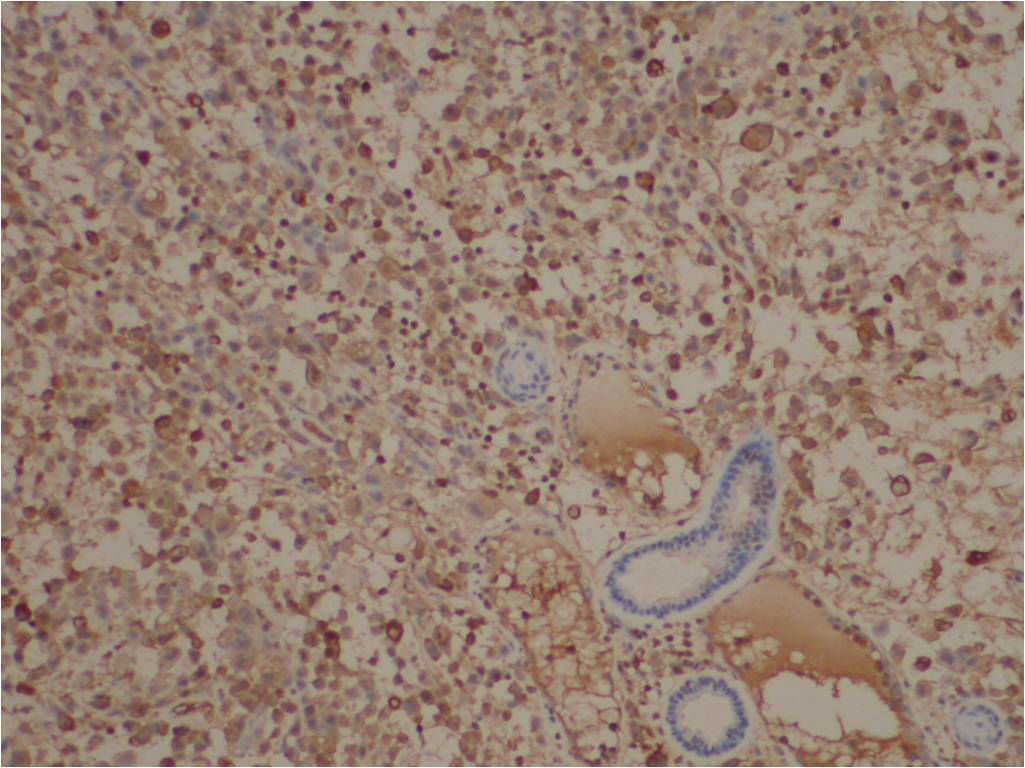

• 图1

• 图2

• 图3

• 图4

• 图5

免疫组化结果:

阳性: CKVimCD34EMA均(+),P63(灶+),CEA个别细胞(+), Ki6770%+)。

阴性: CD31MyogeninMyoD1desminactinCD68LysCK5/6均(-)。

特染: PAS-)。

最后诊断:

(外阴)近端型上皮样肉瘤。 (proximal-type epitheliod sarcoma, PES)